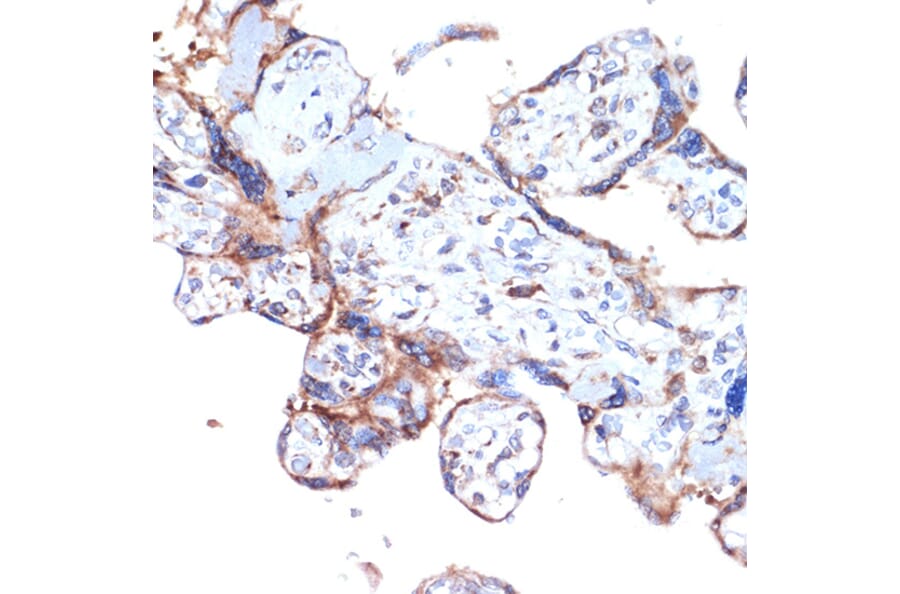

Immunohistochemistry analysis of paraffin-embedded human placenta using Anti-ARTS1/ERAP1 Antibody [ARC2120] (A308078) at a dilution of 1:100 (40x lens). Perform microwave antigen retrieval with 10 mM Tris/EDTA buffer pH 9.0 before commencing with IHC staining protocol.